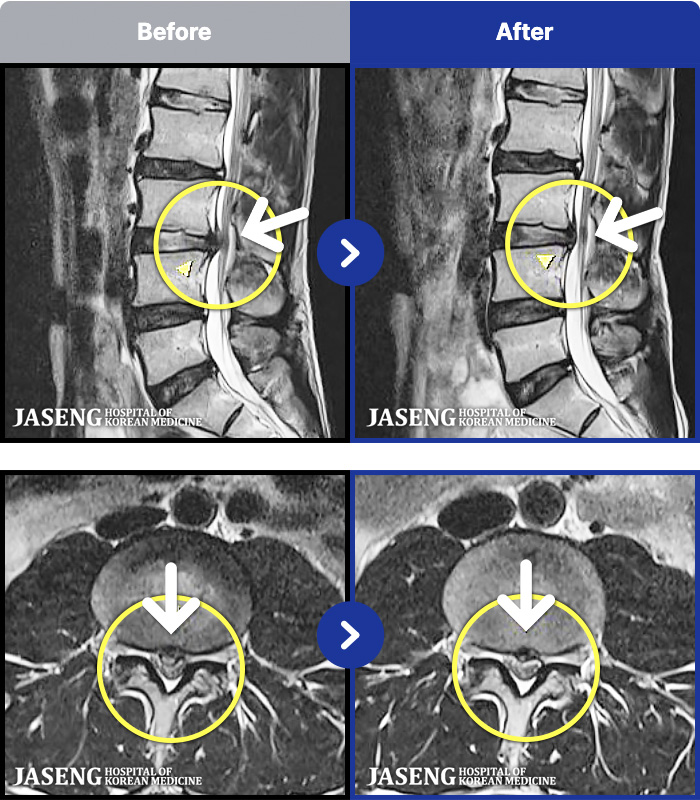

97 MRI ũ ʸ Ȯϼ.

ȯںп Ǹ ǿ ԿǾ, ο ġ ۿ Ƿ ġḦ Ͻñ ٶϴ.